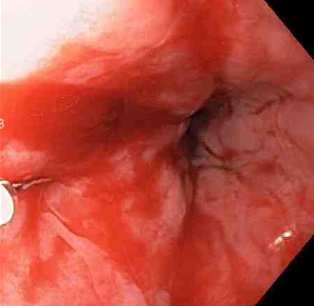

Epinephrine (adrenaline) is injected locally around the site of the Mallory-Weiss tear

From the collection of Juan Carlos Munoz, MD, University of Florida